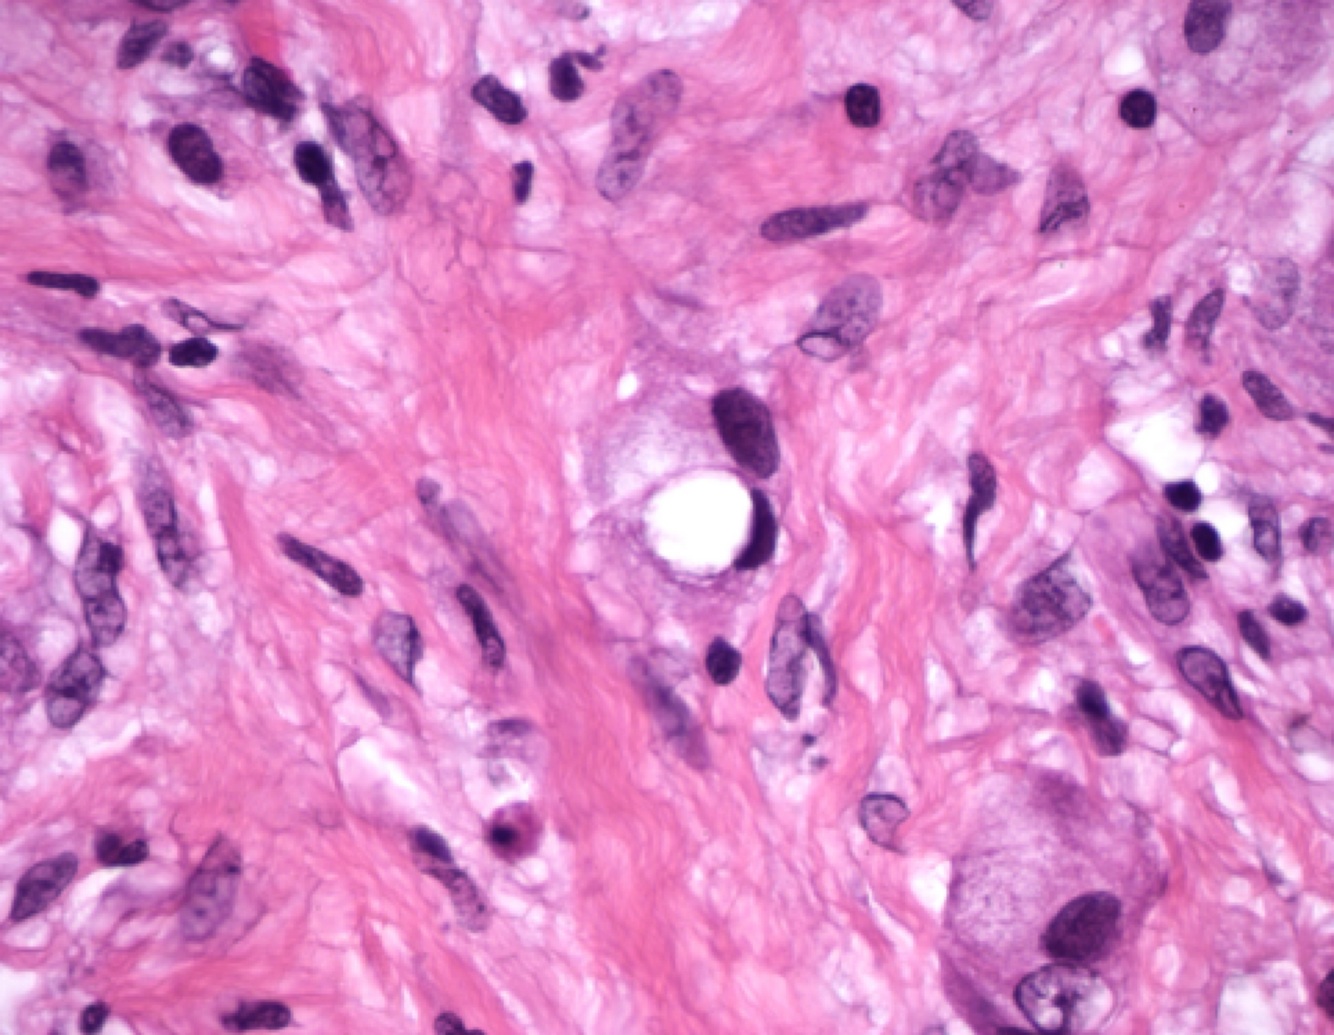

Whipple disease: A biopsy specimen of the lamina propria shows accumulation of macrophages that contain rod-shaped inclusion bodies

Whipple disease: foamy macrophages with periodic acid-Schiff (PAS) positive granules,